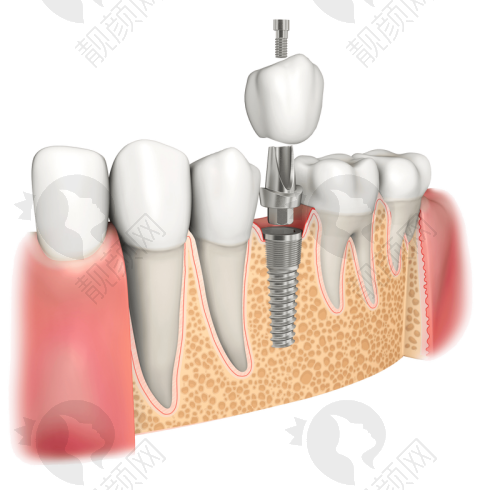

像全口/半口即刻种植、即刻修复、穿颧穿翼种植牙,这些复杂的手术,不是每一家医院都能做得好。但鼎植口腔潜心研究并进行VIIV颧骨种植和穿翼板种植、全口/半口即刻种植、即刻修复,还积累了特别多成功的例子。

比如说VIIV颧骨种植技术,它可用于上颌骨重度骨吸收情况下的口腔种植,不用植骨,也不用长时间等待,而且微出血。这项技术突破了传统种植牙对牙槽骨条件的限制,能为缺骨的患者实现即刻种植、即刻负重。鼎植口腔还把改良颌外颧骨种植技术和VIIV整体解决方案用到临床上,成效非常好。